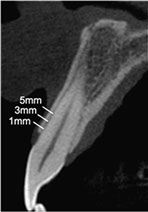

In this article, Araujo & Lindhe conclude that "the placement of Bio-Oss Collagen" in the buccal gap between the implant and the buccal-approximal bone walls of fresh extraction sockets, after an immediate implant, modified the process of hard tissue healing, provided additional amounts of hard tissue at the entrance of the previous socket and improved the level of marginal bone-to-implant contact.

This is quiet controversial, when some years ago, 2001, Paolantonio published that the gap between the implant and bone crest is less than 2 mm, any biomaterial is needed to fill the buccal gap.

Although this sentences and doubts surrounding this trial, every time I go through an inmediate implant I prefer to graft the buccal gap with a biomaterial or autologous bone or even mix both with PRGF® to accelerate and to promote bone formation around the implant